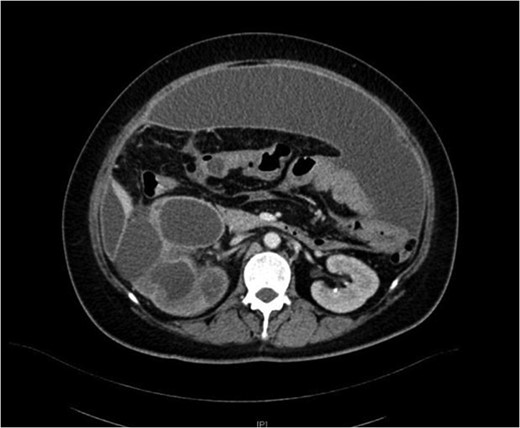

She underwent insertion of a right percutaneous nephrostomy drain, percutaneous drainage of the anterior abdominal collection, as well as a percutaneous biopsy of the right renal soft tissue lesion. Urine cultures from the percutaneous nephrostomy grew Proteus mirabilis. Fluid cytology from the abdominal collection showed acute inflammatory cells. Biopsy of the renal lesion showed xanthogranulomatous inflammation.

Our patient had an atypical presentation with abdominal distension and presumed ascites, which was eventually revealed to be an anterior preperitoneal collection secondary to infection. Although the initial suspicion was that of a malignant process complicated by ascites, subsequent cytology and histopathological results showed that it was likely benign. In view of the non-functioning renal unit and significant abdominal collection, she underwent definitive surgery.

The most common urinary pathogen identified was Escherichiacoli [3], and common areas of involvement were the retroperitoneum and psoas muscle. In our patient, the retroperitoneal space was surprisingly not greatly involved, but rather it was the anterior preperitoneal space that had significant adhesions and inflammation. The pathogen identified from both nephrostomy and preperitoneal collection was P. mirabilis, showing that both pathologies were linked.